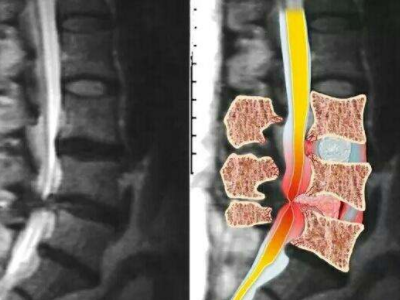

脊柱脊髓神經(jīng)微創(chuàng)中心以微創(chuàng)技術(shù)為引領(lǐng),以功能恢復(fù)為目標(biāo),主要治療脊柱外傷、腫瘤、退行性病變、脊柱畸形等疾病。團(tuán)隊(duì)利用神經(jīng)外科顯微技術(shù),結(jié)合神經(jīng)內(nèi)鏡微創(chuàng)技術(shù),對(duì)脊柱間盤變性疾病、頸腰椎管狹窄、頸腰椎間孔狹窄、頸腰椎間盤突出、頸腰椎體不穩(wěn)、脊柱骨折、寰樞椎脫位、脊柱腫瘤、椎管內(nèi)腫瘤、脊髓損傷、脊髓空洞、脊髓栓系等疾病進(jìn)行高效、特色手術(shù)治療,如顱頸交界區(qū)畸形寰枕減壓內(nèi)固定術(shù)、脊柱腫瘤全脊椎切除內(nèi)固定術(shù)、微創(chuàng)椎管內(nèi)腫瘤切除術(shù)、微創(chuàng)脊柱旁腫瘤切除術(shù)、寰樞椎脫位椎間融合內(nèi)固定術(shù)、脊柱骨折微創(chuàng)經(jīng)皮椎弓根釘內(nèi)固定術(shù)、經(jīng)椎間孔椎間融合內(nèi)固定術(shù)(MIS—TLIF)等,最大程度降低脊柱脊髓手術(shù)創(chuàng)傷,具有創(chuàng)傷小、輸血少、恢復(fù)快、口碑好,出院早等優(yōu)勢(shì)。